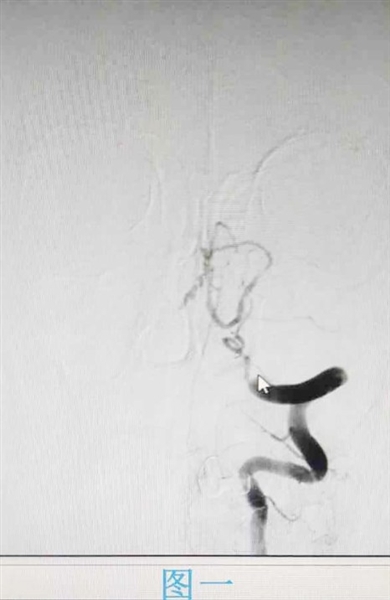

江毅介绍,在卒中中心接诊的患者中,也有不少脑血管重度狭窄的病人。患者张磊因头晕入院,医生对其进行相关检查,通过颈部血管超声显示,张磊左侧锁骨下动脉盗血,完善脑血管造影显示双侧颈内动脉及左侧锁骨下动脉重度狭窄。经过介入支架手术治疗后,张磊恢复良好并出院。